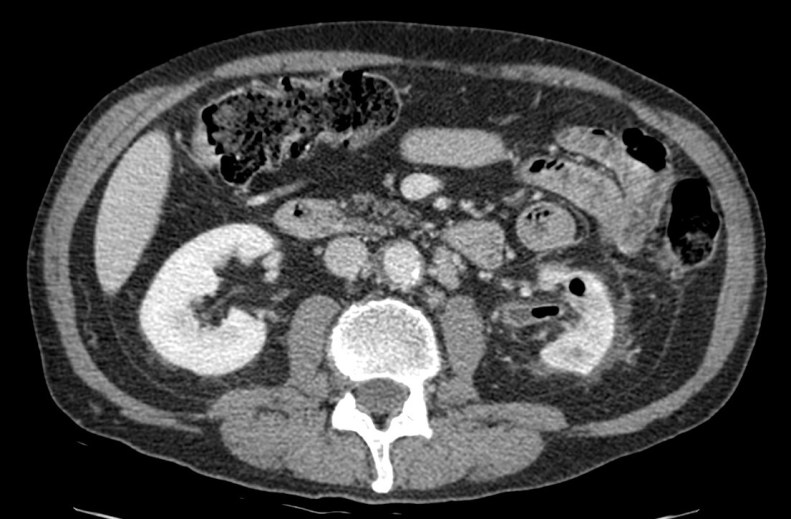

Tomografía computarizada:

- Técnica de elección.

- Agrandamiento y destrucción parenquimatosa.

- Burbujas o tractos lineales de gas.

- Colecciones líquidas y focos de necrosis con o sin abceso.

- Obstrucción renal.

La TC nos permite clasificar la severidad de la PE.

- Grado I: gas en el sistema colector (pielitis enfisematosa)

- Grado II: gas en el parénquima renal sin extensión al espacio extrarenal

- Grado III: a)Extensión del gas o abceso al espacio perirenal. b)Extensión del gas o absceso al espacio pararenal y/o extensión a tejidos adyacentes (psoas…)

- Grado IV: bilateral o pielonefritis enfisematosa en riñón único.